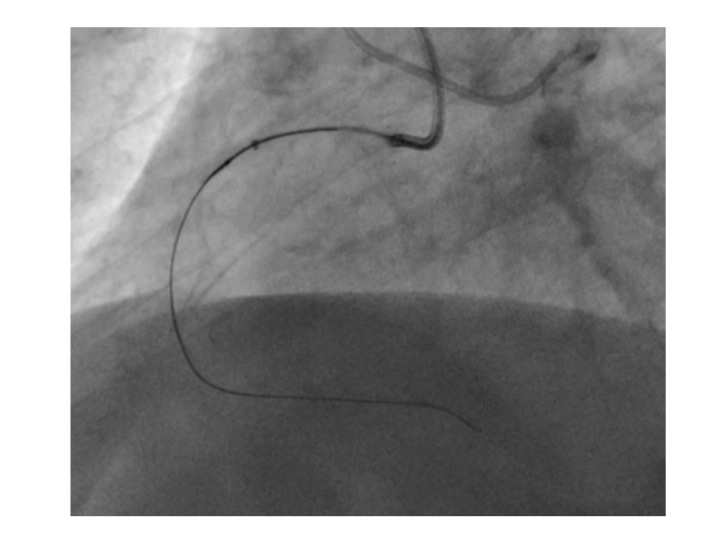

After beginning medical treatment with atorvastatin, carvedilol and acetylsalicylic acid the patient presented only a slight improvement, so we decide to add clopidogrel and perform a percutaneous revascularization of the total chronic occlusion. Angioplasty was successfully performed (Figures 4-6), with the implantation of two everolimus DES (drug-eluting stents). The patient had a good clinical evolution with total disappearance of the symptomatology.

Figure 5 PCI procedure in a chronic total occlusion of the proximal right coronary artery with a coronary wire and a guide catheter extension.